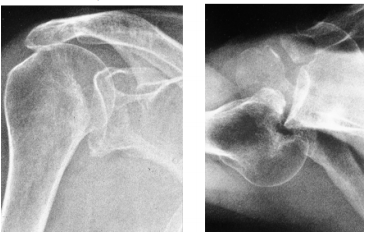

72 一位 25 歲年輕男性,車禍跌倒右肩膀著地後,右肩關節疼痛且關節運動受阻,右肩之正面(AP view) 及腋下(axillary view)之 X 光攝影如下圖,該病人的肩膀外傷診斷為何?

(A) humerus fracture and dislocation (B) shoulder anterior dislocation and impaction (C) shoulder posterior dislocation and impaction (D) post-traumatic arthritis